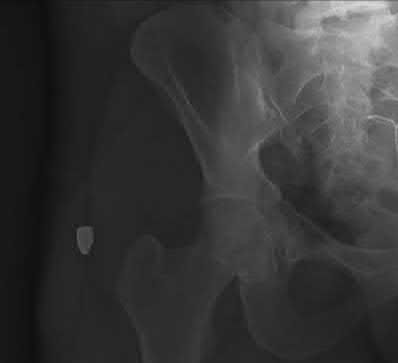

Question 12:

A 13-year-old obese male complains of left knee pain and a limp for 3 weeks. Radiographs are provided: He is able to bear weight with crutches. During physical examination, as the affected hip is passively flexed, into which position will the limb obligately deviate?

Correct Answer: External rotation

Explanation:

In slipped capital femoral epiphysis (SCFE), the proximal femoral epiphysis displaces posteriorly and inferiorly relative to the femoral neck. This altered anatomy leads to an obligate external rotation of the thigh during passive hip flexion, a classic physical examination finding.